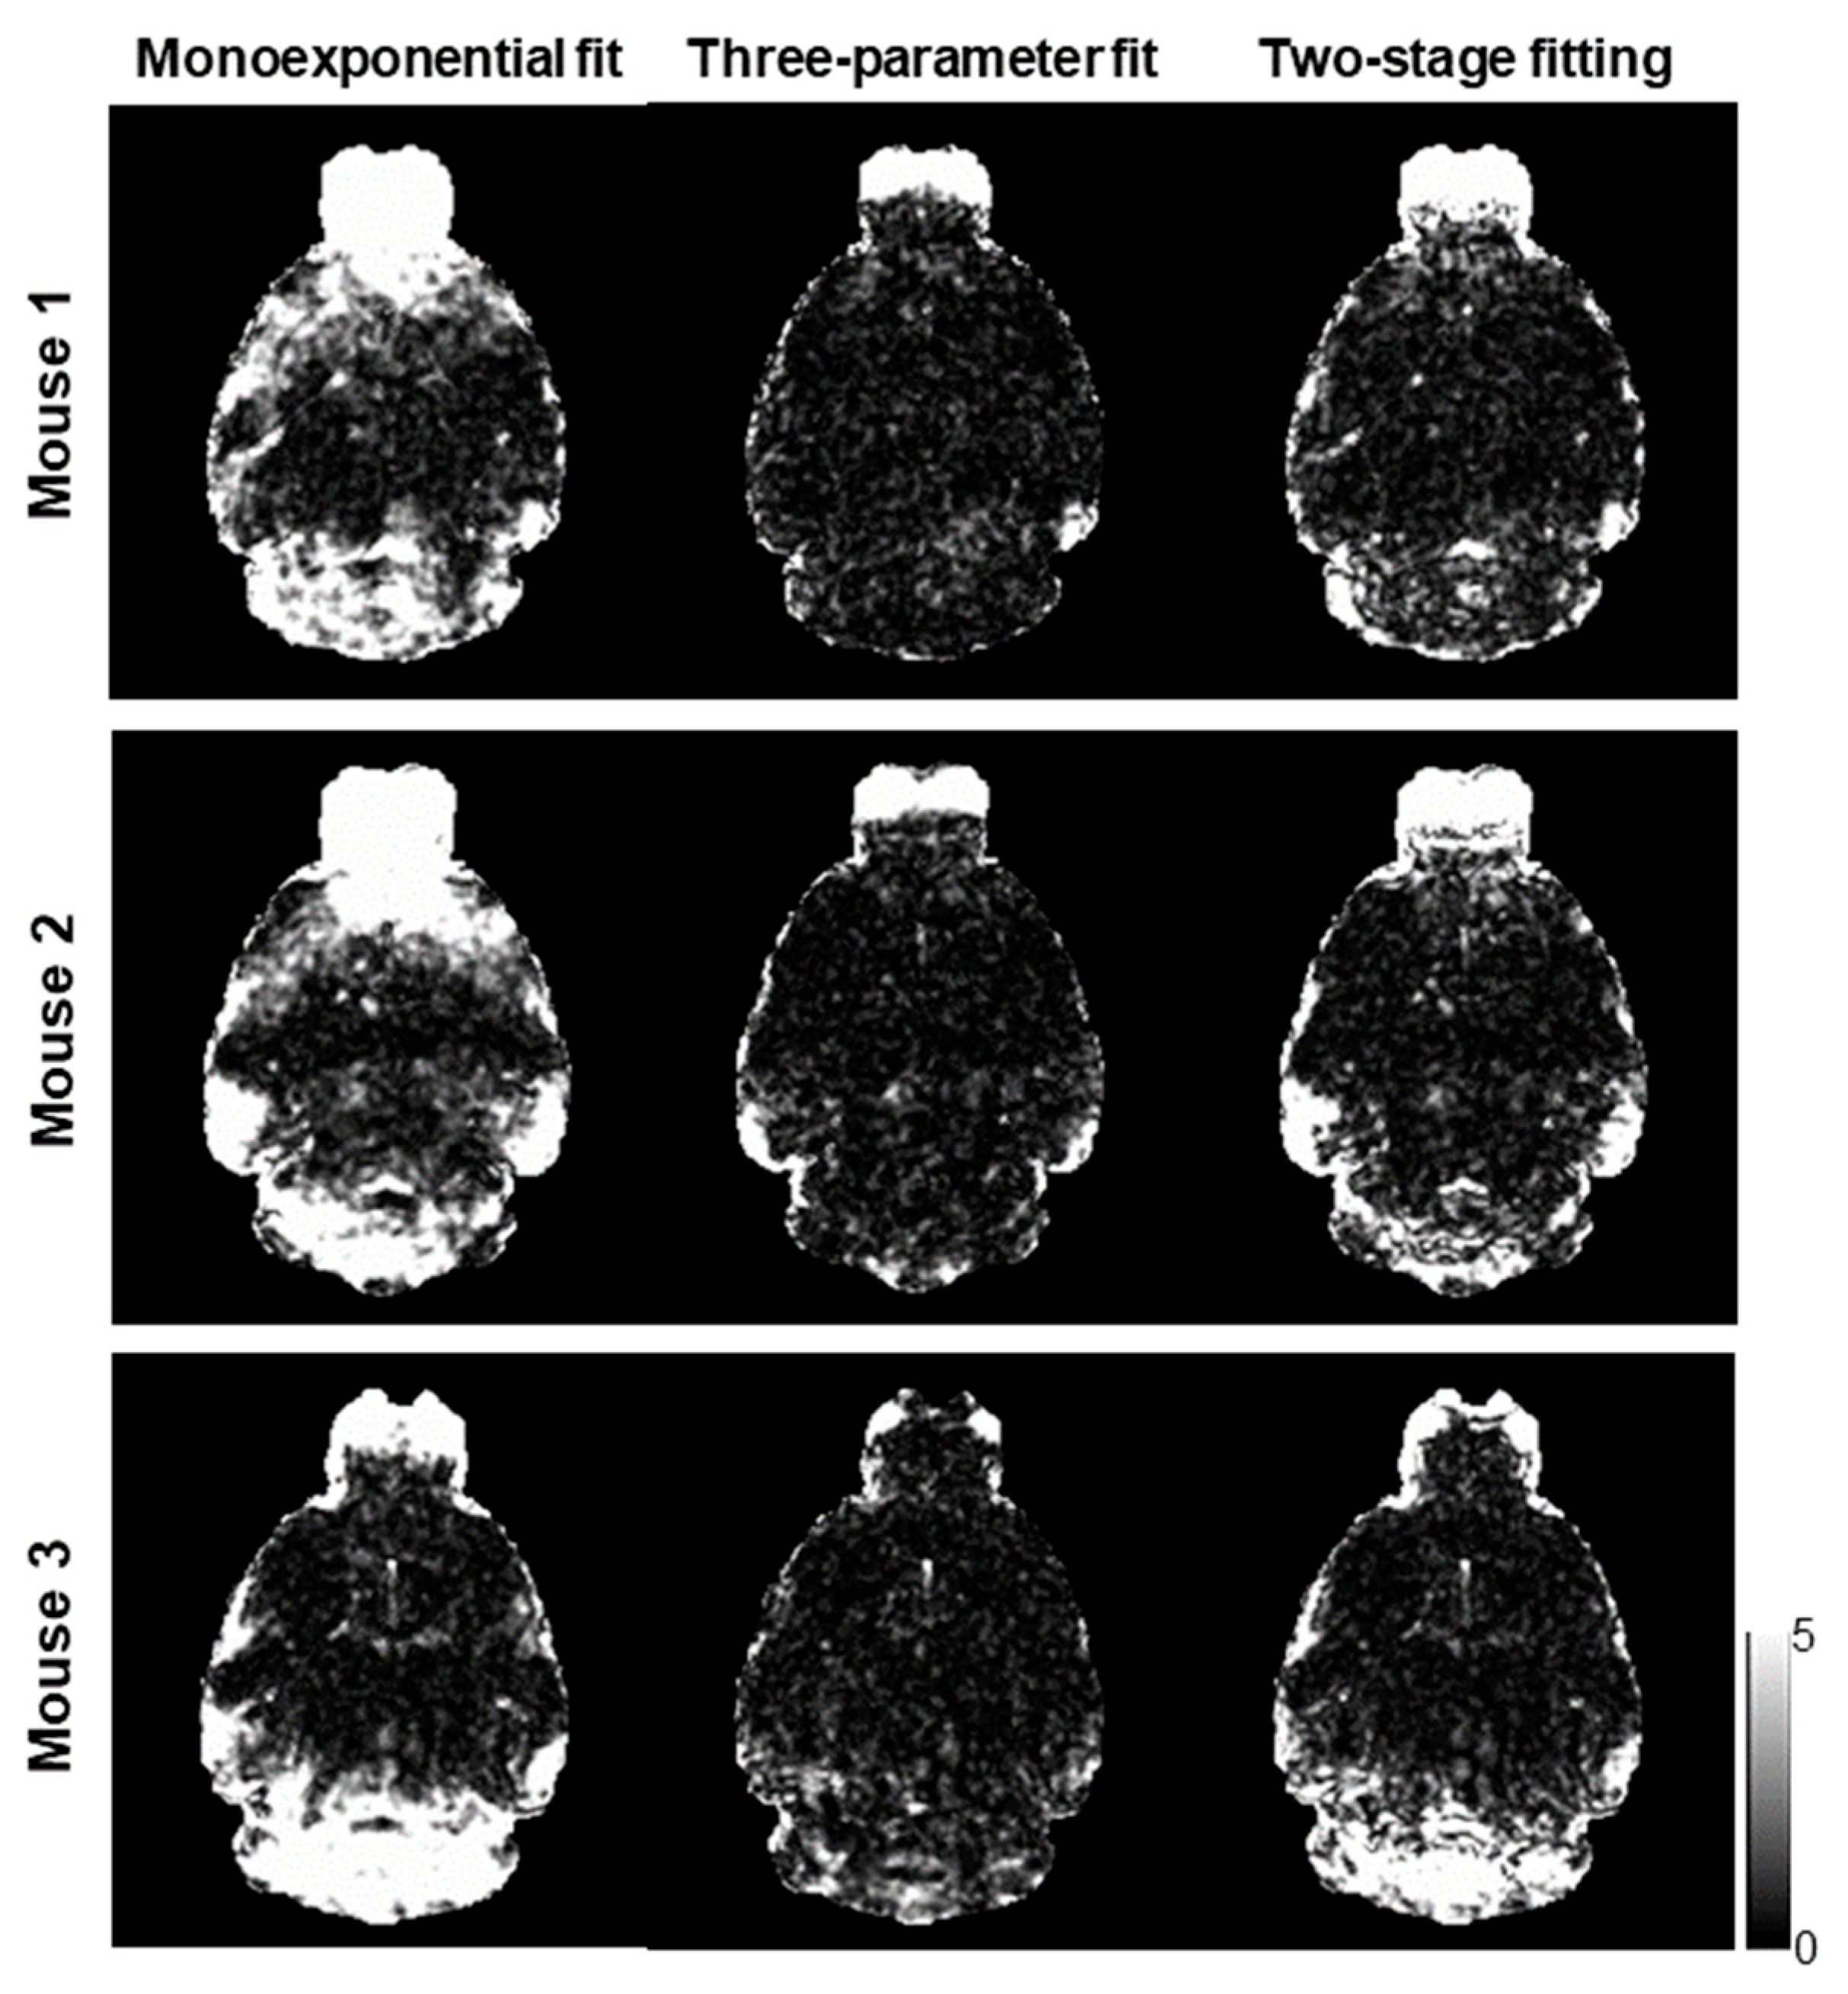

Figure 3. χ ν 2 maps corresponding to the voxel-wise fittings using the monoexponential model, three-parameter model, and two-stage fitting procedure, respectively, to generate the R 2 * measurements as shown in Figure 2.

Figure 2 shows the computed R 2 n o c o r r * , R 2 c o r r * , and R 2 c o r r _ t * maps of three mice using the monoexponential model, three-parameter model, and two-stage fitting procedure. Figure 3 shows the corresponding χ ν 2 maps using the three fitting methods. R 2 n o c o r r * showed the ΔB0-induced increases in the regions near air–tissue interfaces, where fitting residuals of the monoexponential fit were elevated. These ΔB0 effects were consistently mitigated on the R 2 c o r r * and R 2 c o r r _ t * maps. Furthermore, the noise effect on the R 2 c o r r * maps was mitigated on the R 2 c o r r _ t * maps without compromising the contrast of the brain structure.